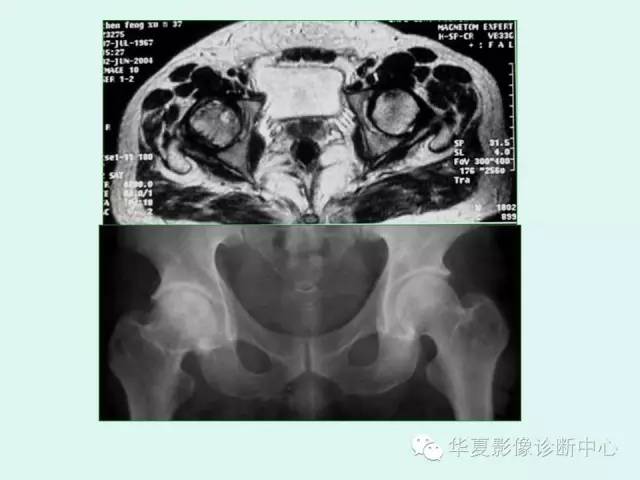

【PPT】股骨头缺血性坏死